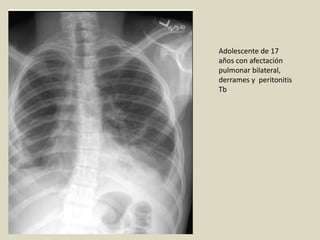

Adolescente de 17

años con afectación

pulmonar bilateral,

derrames y peritonitis

Tb